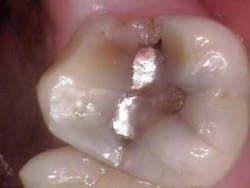

Such is the case for the patient who presented with a chief complaint of biting and occasional slight cold sensitivity on his upper right back molar (No. 2). The patient stated that it hurt to chew and that he wanted to get his tooth fixed as soon as possible. Upon radiographical examination, the periapical for No. 2 was normal. Clinically, the tooth presented with a conservative occlusal amalgam with caries distal to the restoration. In addition, a fracture line on the mesial and distal marginal ridges was noted. Percussion and cold testing were normal and periodontally, the tooth was stable. Bite assessment with the tooth sleuth revealed a positive response on the lingual cusp when biting and releasing. Diagnosis: reversible pulpitis secondary to a crack.

Due to the separation of the buccal and lingual cusps, a crown was recommended to restore the tooth to full form and function. In addition, the patient was informed that the fracture line likely extended further than the naked eye could observe; excavation of the tooth would reveal more detail. (1)